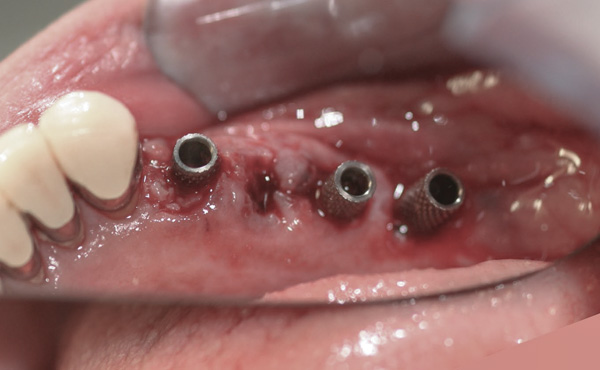

Background: In this case, the patient had a failing mandibular and maxillary dentition due to caries secondary to radiation-induced xerostomia. The patient had had a radical neck dissection to remove a squamous cell carcinoma of the throat 9 years prior to his prosthodontic consultation with the authors. The patient reported a history of radiation therapy following surgery, but did not have a shielding stent. A staged approach was used so as to avoid removable prosthetics on his severely dry soft tissues. He chose to treat his mandibular issues first. Figure 9 shows healing abutments next to the temporarily retained natural teeth, and Figure 10 shows the first-stage custom abutments inserted with relatively good gingival contour and no recession. Recession was clearly seen around all first-stage abutments following adjacent extractions and second-stage implant placement (Figure 11).

Results: The decision was made to remove these abutments and make a fixture-level impression of all the implants so that both new and first-stage abutments could be milled together for parallelism and proper gingival margin location. Because this requires the removal of the first-stage abutments that were retaining the provisional prosthesis, temporary abutments were placed prior to removal of all custom abutments in order to assure proper seating and vertical dimension of the provisional. These temporary abutments then retained the provisional while all custom abutments were fabricated and/or milled in the laboratory. Figure 12 shows the placement of the remilled (first-stage implants) and new (second-stage implants) custom abutments.

Figure 9 Healing abutments.

Figure 9

Figure 10  First-stage custom abutments.

Figure 10

Figure 11 Recession evident around first-stage abutments following adjacent extractions and second-stage implant placement.

Figure 11

Figure 12 Remilled and new custom abutments.

Figure 12